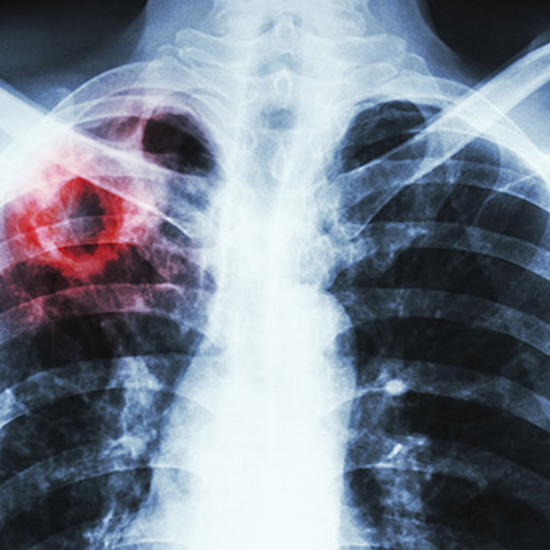

Туберкульоз залишається загрозою для глобального громадського здоров’я і є головною інфекційною причиною смерті в усьому світі. У 2018 р. приблизно 10 млн осіб захворіли на туберкульоз, а 1,5 млн — померли від цієї хвороби. Щонайменше 1 млн дітей хворіють на туберкульоз щороку. У 2018 р. від туберкульозу померли близько 205 тис. дітей. За оцінками близько 500 тис. нових випадків туберкульозу з мультирезистентністю та резистентним до рифампіцину (MDR/RR-TB) виникають щороку, але лише один із трьох випадків зареєстровано країнами, які мали діагностувати та лікувати у 2018 р.